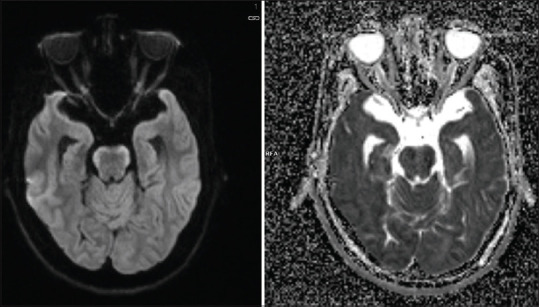

"Bloomy Rind on Cheese Sign" - A Radiological Biomarker of Leptomeningeal Metastasis.